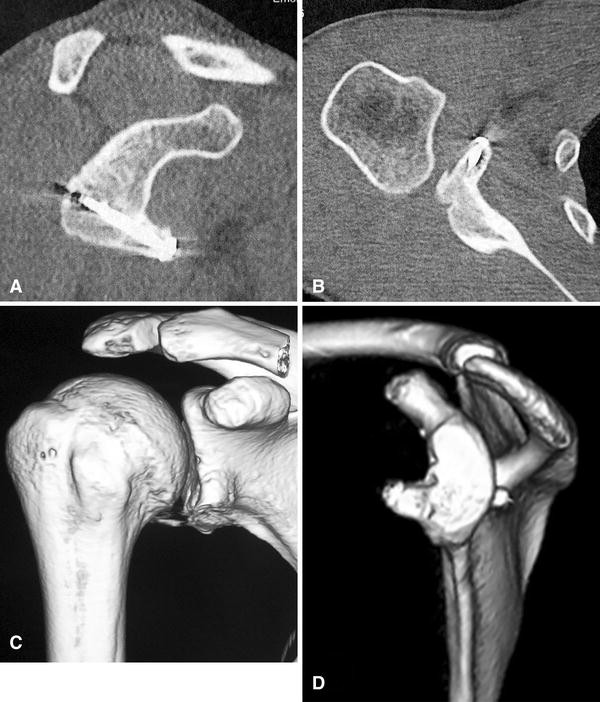

Postoperative radiograph after the Bristow Latarjet repair (at 43... Download Scientific Diagram

Postoperative radiograph after the Bristow Latarjet repair (at 43... Download Scientific Diagram Bristow Repair the bristow procedure, and its variants, describes transfer of the coracoid process through the subscapularis tendon as. the current method of modified arthroscopic bristow procedure with screw fixation without subscapularis split reduces surgical time, reduces the risk of nerve damage consequences, and is simple to apply. the bristow procedure, and its variants, describes transfer of the coracoid. Bristow Repair.